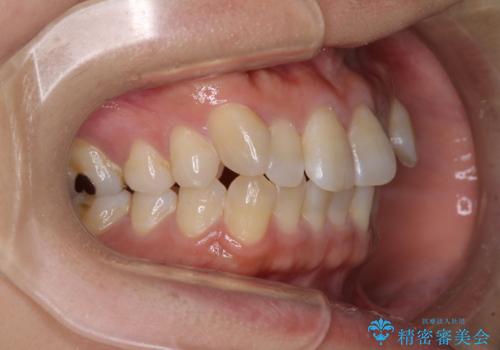

気になる八重歯 ワイヤー装置での非抜歯矯正

- 上顎の八重歯と全体的なデコボコを気にして来院された患者様です。

口元の突出感はなかったため非抜歯矯正での対応となりますが、八重歯を改善する際に上顎前歯が前突する可能性があったため、上顎臼歯部にアンカースクリューを使用して、歯列が前方に転位しないようにすることとしました。

また舌のトレーニングを行うことで、上顎前歯の突出予防や上下前歯に隙間ができなくなるようにしました。

ワイヤー矯正でもインビザラインでも対応可能でしたが、上顎歯列が前方位であるときには、ワイヤー矯正の方がより良い仕上がりとなる可能性が高いため、ワイヤー矯正をおすすめいたしました。